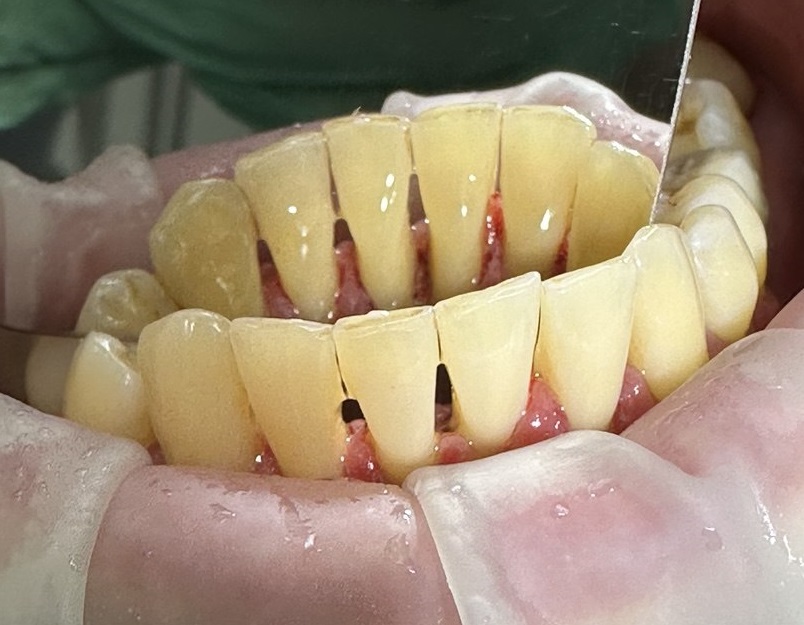

Проблема

Пациент обратился с жалобами на зубной налет, наличие зубного камня на передних зубах нижней челюсти.

Решение

Проведена профессиональная гигиена полости рта (AirFlow). Удален зубной камень и налет. Пациент доволен!